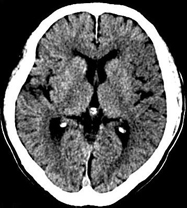

目前臨床對于16層CT的認可主要集中在三維成像領域上的突破.在16層CT的產品平臺上,常規(guī)掃描就能實現(xiàn)滿足三維成像的要求,因此16層也被稱為三維CT,三維成像給臨床診斷帶來了更精確更豐富的診斷信息,我們以臨床為例:

如上圖所示,相鄰的三張軸位圖像未見明顯異常,根據(jù)傳統(tǒng)軸位圖像很難得到準確的臨床診斷。

同一病人利用容積數(shù)據(jù)進行三維處理后,高品質MPR和三維圖像上則清晰顯示了縱向排列的腹腔干與腸系膜上動脈相鄰近,血管發(fā)生變 異,近端血管閉塞,為臨床提供了精確的診斷信息。